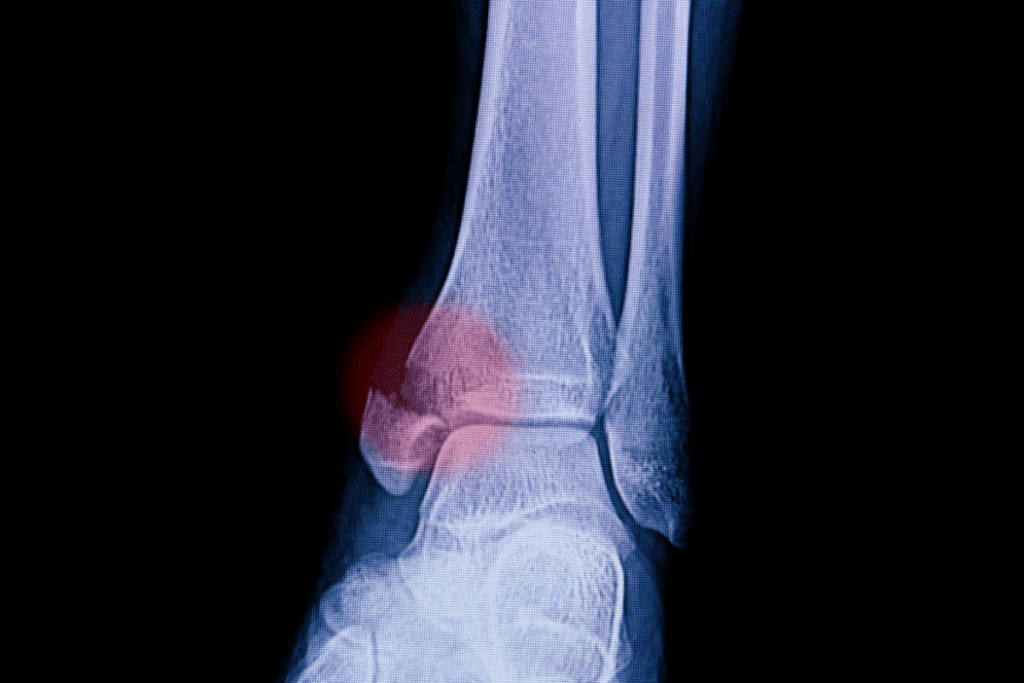

| Ankle | 4-8 weeks | 6-12 weeks |

Ankle and Foot Fractures

Ankle and foot fractures can take 6 to 12 weeks or more to heal. This depends on how bad the fracture is and where it is.

A simple ankle fracture might heal in 6 weeks. But, more serious fractures or those in the foot can take up to 3 months or more.